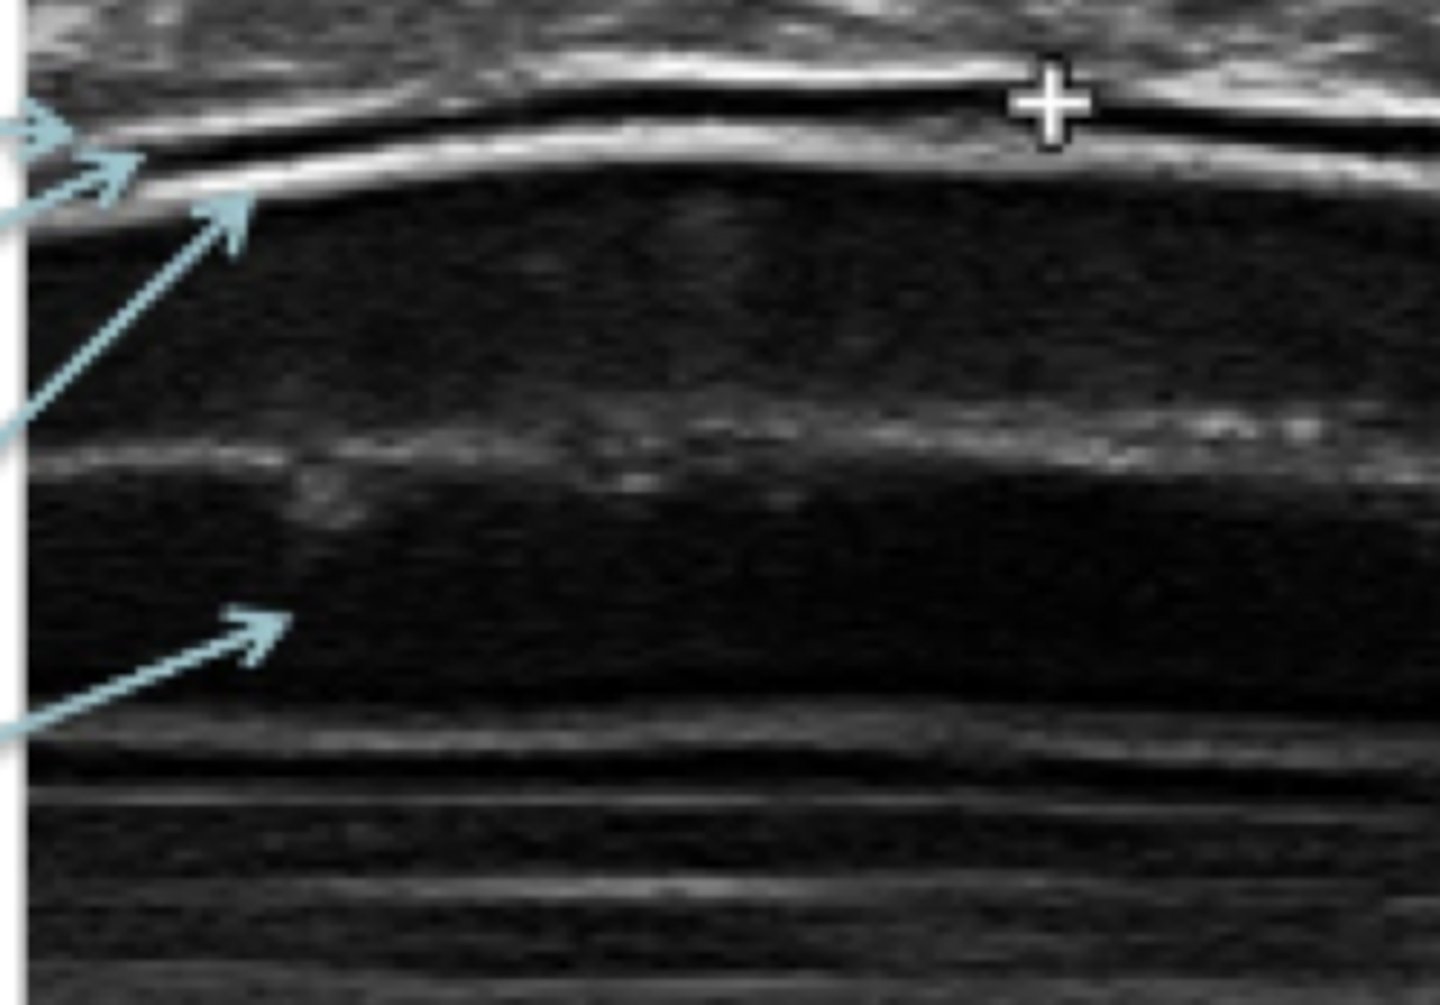

megacolon

patología: